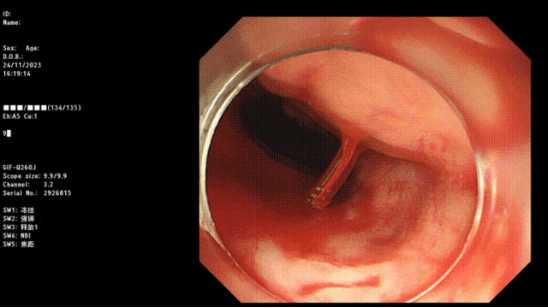

入冬以來,消化道出血進入高發(fā)期。近期,臨沂金鑼醫(yī)院消化內(nèi)科收治了多例急性消化道出血患者,消化內(nèi)科主任姜開通(醫(yī)師)提醒:寒冷季節(jié),誘發(fā)部分有消化道疾病患者病情發(fā)作,特別是消化道出血,患者通常發(fā)病急、出血量大、可伴有失血性休克,甚至危及生命,請及時就醫(yī),送醫(yī)途中,嘔吐時盡量側(cè)臥,避免誤吸。

金鑼醫(yī)院消化內(nèi)科有多種消化道止血方法,不用開刀,不用外科手術,傷害更小,效果更好,有癥狀早發(fā)現(xiàn),早治療,為您的健康保駕護航。

上消化道出血